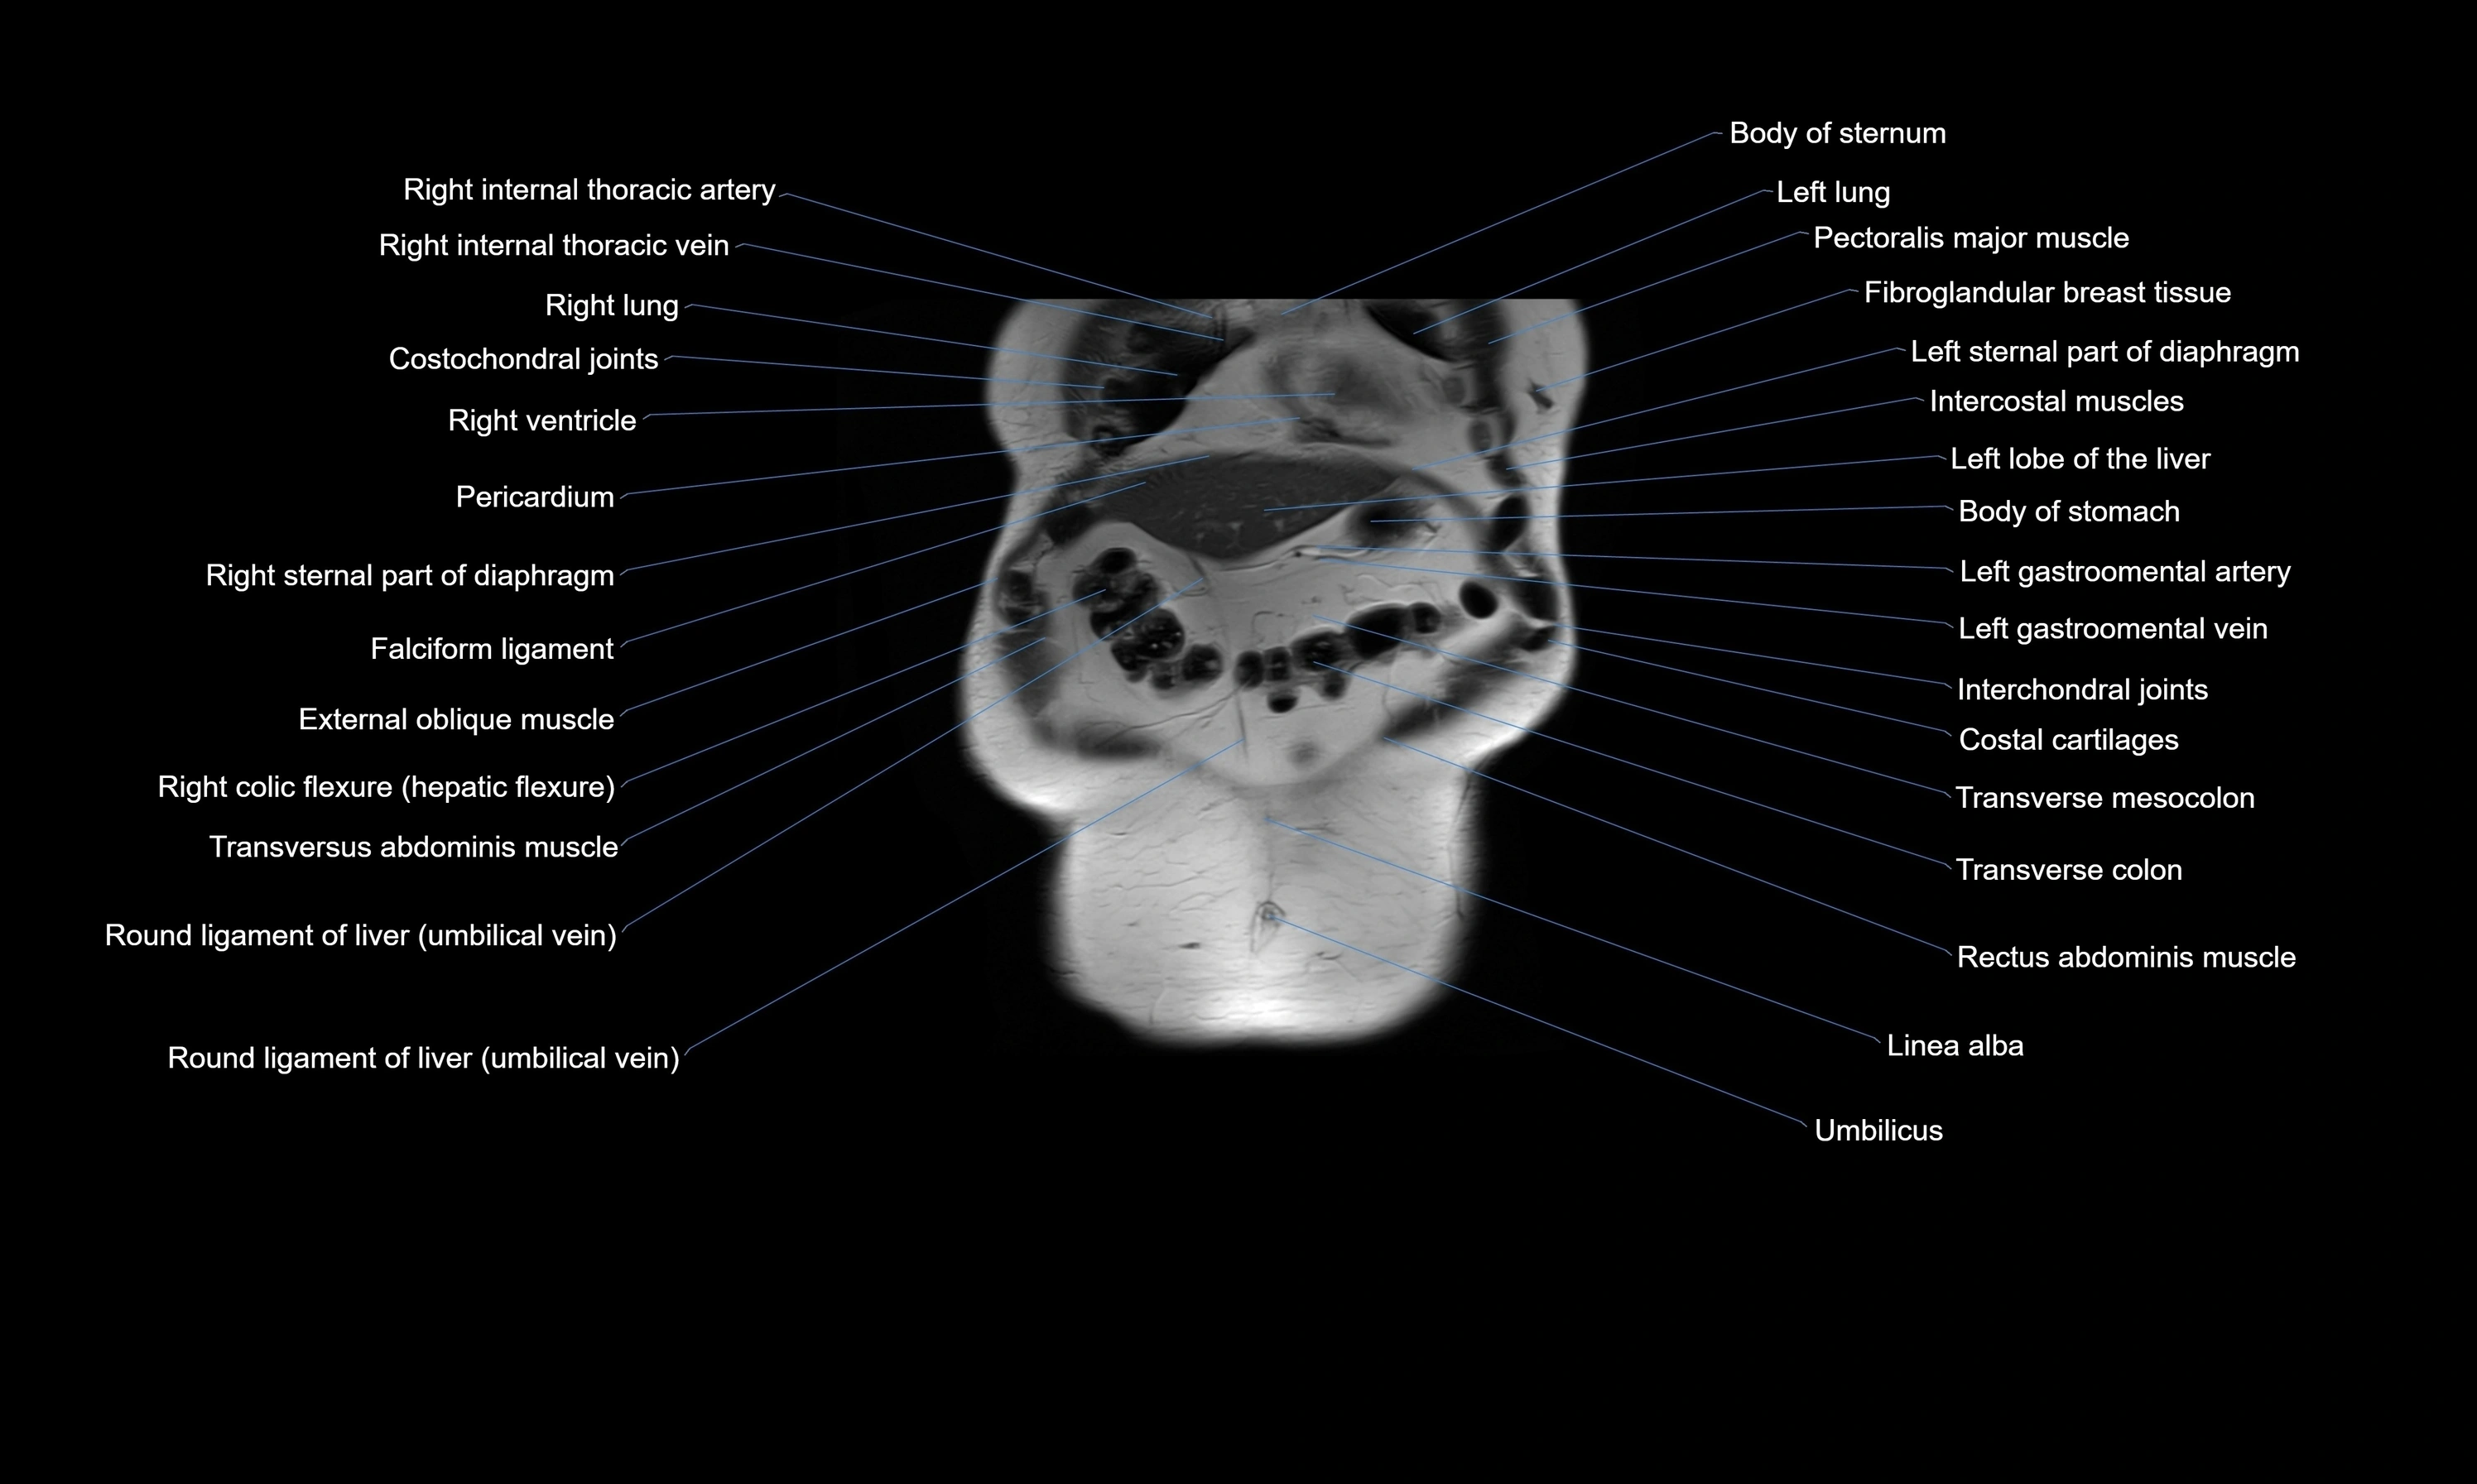

MRI images